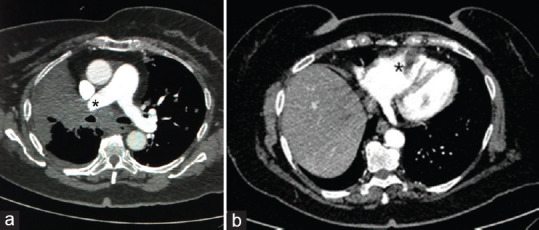

Heart metastatic tumors are more frequent than primary heart tumors. Cardiac metastasis is a rare phenomenon, occurring mainly by direct spread, especially from lung cancer. Cardiac metastases may be asymptomatic or cause arrhythmias, nonspecific electrocardiographic alterations, or mimic a myocardial infarction. In this case report, we illustrate a rare case of pulmonary adenocarcinoma, which through the bloodstream developed a stalactite-shaped metastasis within the right ventricle of conspicuous size (20 mm × 34 mm × 12 mm). In addition, the tumor compressed the right pulmonary trunk, causing pulmonary hypertension. It is essential to characterize metastasis with multimodality imaging. Such lesions within the right cavities can cause massive pulmonary embolism, as in our case, leading to the patient's death, thrombolytic therapy not being effective.